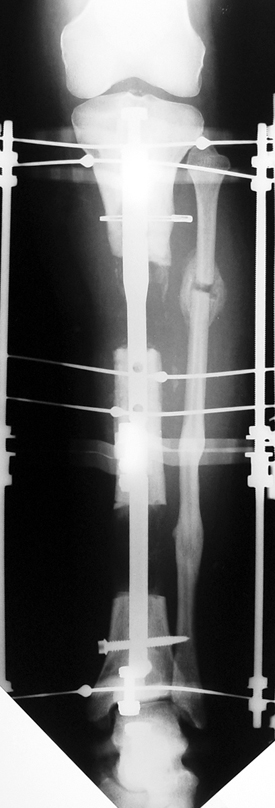

Uygun radikal debridman tüm nekrotik kemik ve yumuşak dokuların çıkartılmasını gerektirir, ve sıklıkla uzuvda instabiliteye neden olur. Kalan kemik ve yumuşak doku defektinin bir şekilde fiksasyonu ve rekonstrüksiyonu gereklidir. İlizarov’un ortaya koyduğu distraksiyon osteogenezi yöntemi, kaynamanın elde edilmesi, deformitenin düzeltilmesi, bacak boy eşitsizliğinin giderilmesi ve segmental defektlerin rekonstrükte edilmesi için başarıyla kullanılmaktadır.

Eksternal fiksatör ile geçen süre (eksternal fiksasyon indeksi), gereken distraksiyon miktarına bağlıdır ve bu süre boyunca bazı komplikasyonlarla karşılaşılabilir. Distraksiyon dönemi sona erdikten sonra, distraksiyon süresinin iki katını aşan konsolidasyon döneminde hastalar eksternal fiksatörü zorlukla tolere edebilirler. Yeterli konsolidasyon sağlanmadan eksternal fiksatör çıkartılırsa ise kırıklar, deformite ve kısalık oluşabilir. Hastanın fiksatör ile birlikte geçirdiği sürenin azaltılması ve böylece hasta konforunun ve aktivite düzeyinin arttırılması için intramedüller çivi üzerinden uzatma yöntemi uygulanmaktadır. Bu yöntemde distraksiyon dönemi sona erdiğinde kemiğin içindeki çivi statik olarak kilitlenmekte ve eksternal fiksatör çıkartılmaktadır. Stabilizasyon intramedüller çivi tarafından sağlandıktan sonra konsolidasyon dönemi gerçekleşmektedir. Bu şekilde hem eksternal fiksatörün uzun süre kalmasından hem de erken çıkartılmasından kaynaklanan komplikasyonların önüne geçilmektedir.